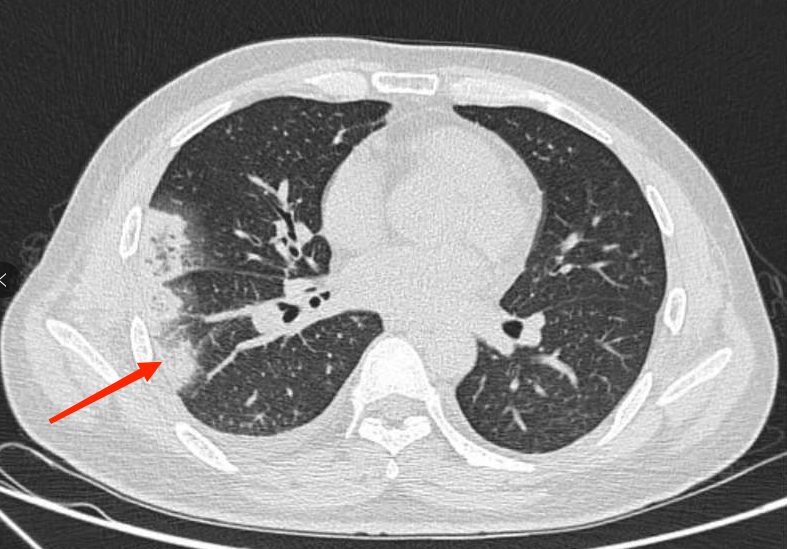

为尽快找到病因,肾内科紧急邀请肺部感染疾病专家团队——呼吸与危重症医学科三区专家前往会诊,专家对患者的肺部影像进行研究后,发现患者肺部病变部位周围可见“晕征”(环绕在病灶周围的磨玻璃影,而这对于感染来说最多见于肺曲霉菌病),专家们对曲霉菌感染在心中打了个问号。

考虑到杨先生病情较为复杂,呼吸与危重症医学科三区立即组织了多学科联合会诊。会上,专家们仔细回顾患者病史,他既往曾有颅内静脉血栓形成,且血脂远高于正常,高血脂的病人血液粘稠、流速缓慢,而这正是血栓形成的高危因素。杨先生的胸痛伴有咯血痰,肺部影像学改变为尖端指向肺门的阴影,除了肺部感染外,还有一个很重要且最容易让人忽视的疾病——肺栓塞!

不放过任何一个可疑因素,杨先生在医护人员的陪同下完善了肺动脉CTA检查,检查结果出来,果然是肺栓塞!杨先生肺部那一片片密度增高带有晕征的病变,以及抗感染治疗无效的疑点都得到了解释,是肺栓塞导致了肺梗死。

▲ 肺动脉CTA提示:肺栓塞